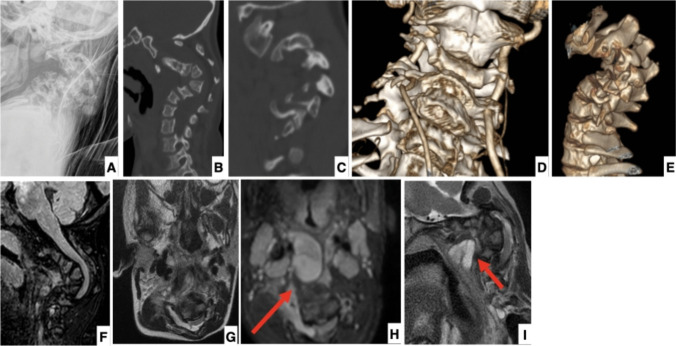

Purpose: We faced and herein report a detailed description of pre-operative assessment, management, and post-operative follow-up of a 2-year and 10-month-old girl with neurofibromatosis 1 (NF1) who presented with severe, dystrophic, cervical kyphosis (170 degrees) associated with extensive pre- and para-vertebral plexiform neurofibromas, who also went under MEK inhibitors therapy. Cervical kyphosis in NF1 is particularly rare, and there is no extensive literature available on the subject in terms of clinico-radiological features, surgical approach, and outcomes. We therefore also performed a comprehensive review of the available literature on the topic.

Results: Our patient underwent a first-stage halo-gravity traction followed by a single-stage occipito-cervical posterior fusion. The six-week traction resulted in a reduction of the deformity from 170 to 90°. A further amelioration was obtained by surgery with a final 60% correction of the curvature (69° at last post-operative X-ray). No complications were observed at 1-and-a-half-year follow-up. The plexiform neurofibromas were treated with MEK inhibitors: trametinib for 1 year and 11 months until performing halo traction, and with selumetinib after surgery. We just found 19 papers suitable according to our selection criteria.